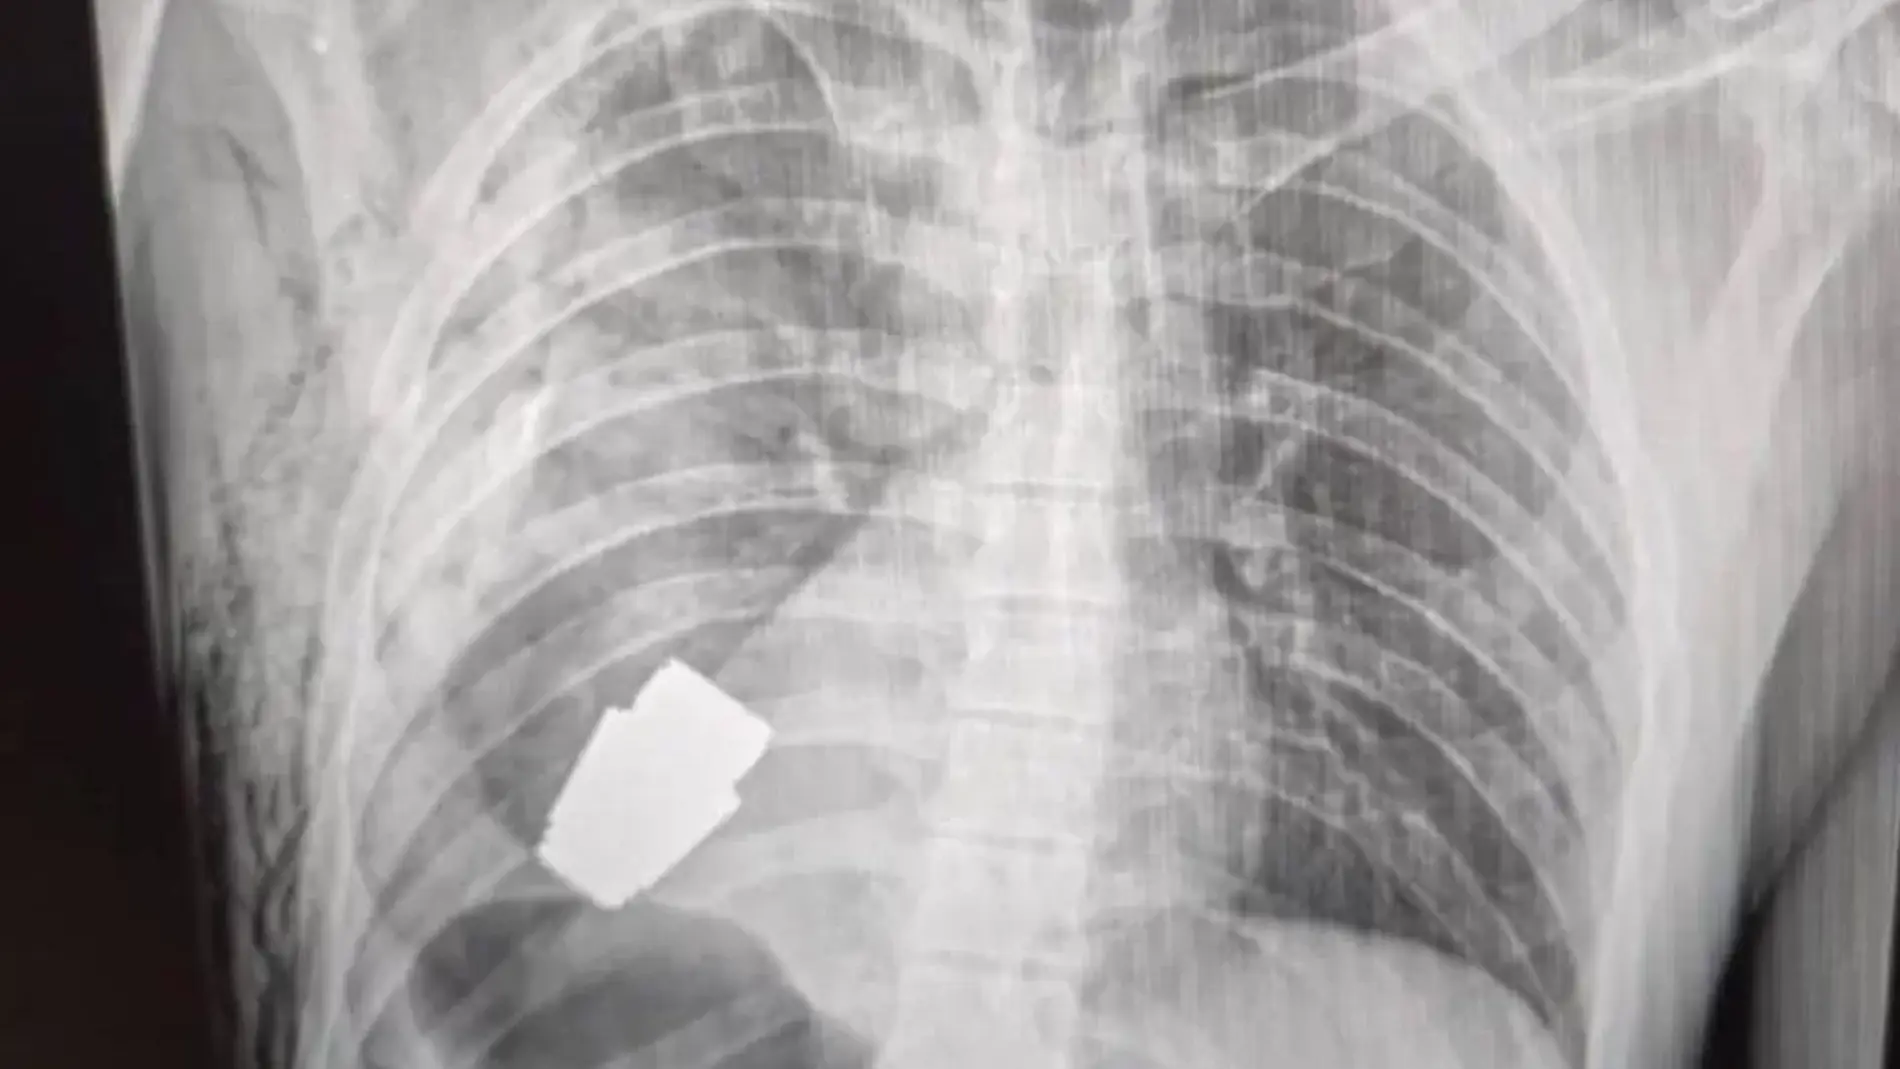

Las fotos en la página de Facebook del servicio médico de las fuerzas armadas de Ucrania muestran una radiografía del explosivo cerca del corazón del militar y otra del cirujano sosteniendo el dispositivo.

No se sabe cómo se alojó la granada en el pecho del soldado, pero las granadas VOG, que miden alrededor de 4 cm de largo, pueden dispararse a una distancia de hasta 400 metros.